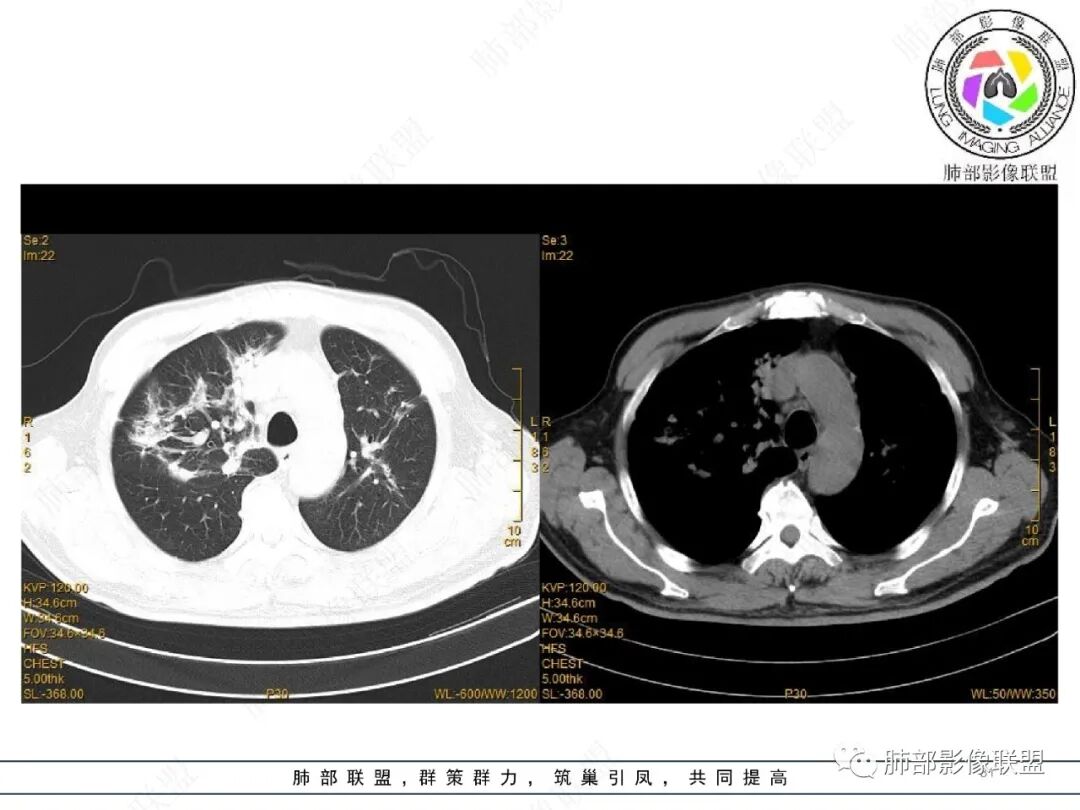

2022.2.17CT显示两肺中内带多发结节影、斑片影、条索影,部分病灶侧向融合与胸膜平行。部分病灶沿着支气管血管束分布、其内支气管稍扩张。部分病灶呈反晕征。大部分病灶边界显示清晰,部分病灶周围可见边界不清的GGO。2022.4.12CT显示两肺中内带多发结节影、条索状、条带状高密度影,边界收缩平直凹陷,大部分病灶沿着支气管血管束分布,亦有位于胸膜下侧向融合与胸膜平行的病灶。总体与第一次CT对比两肺病灶明显吸收。